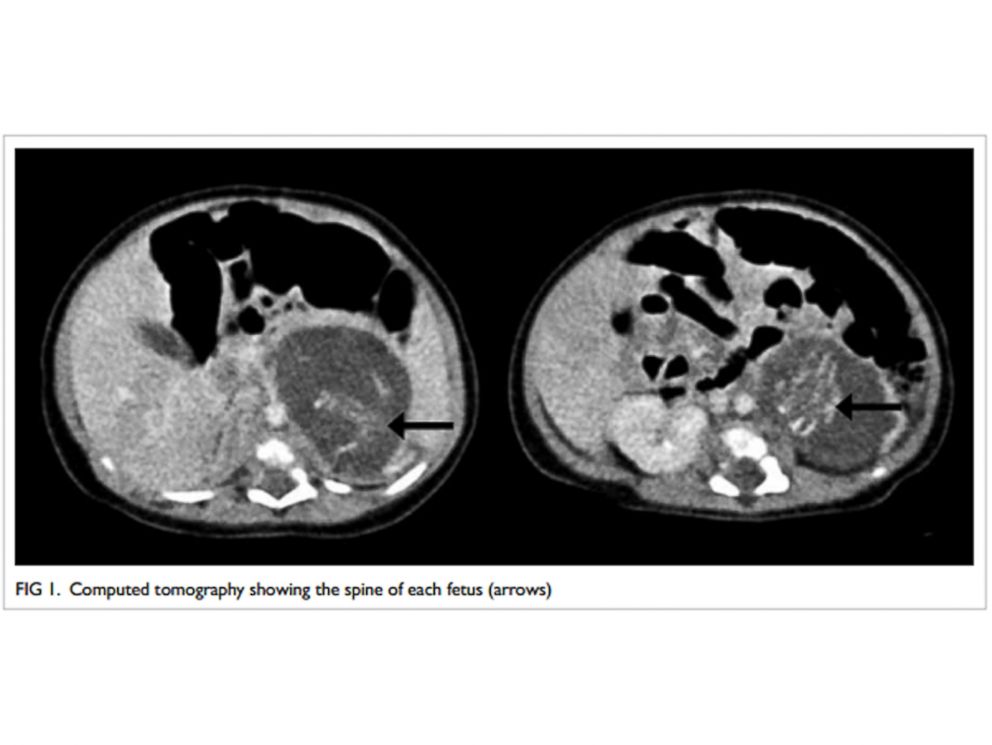

Πιο συγκεκριμένα, τα έμβρυα ζύγιζαν 14 γρ. και 10 γρ. αντίστοιχα, και η ανάπτυξή τους είχε προχωρήσει αρκετά ώστε να έχουν το καθένα 4 άκρα, σπονδυλική στήλη, θώρακα, έντερα και πρωκτό.